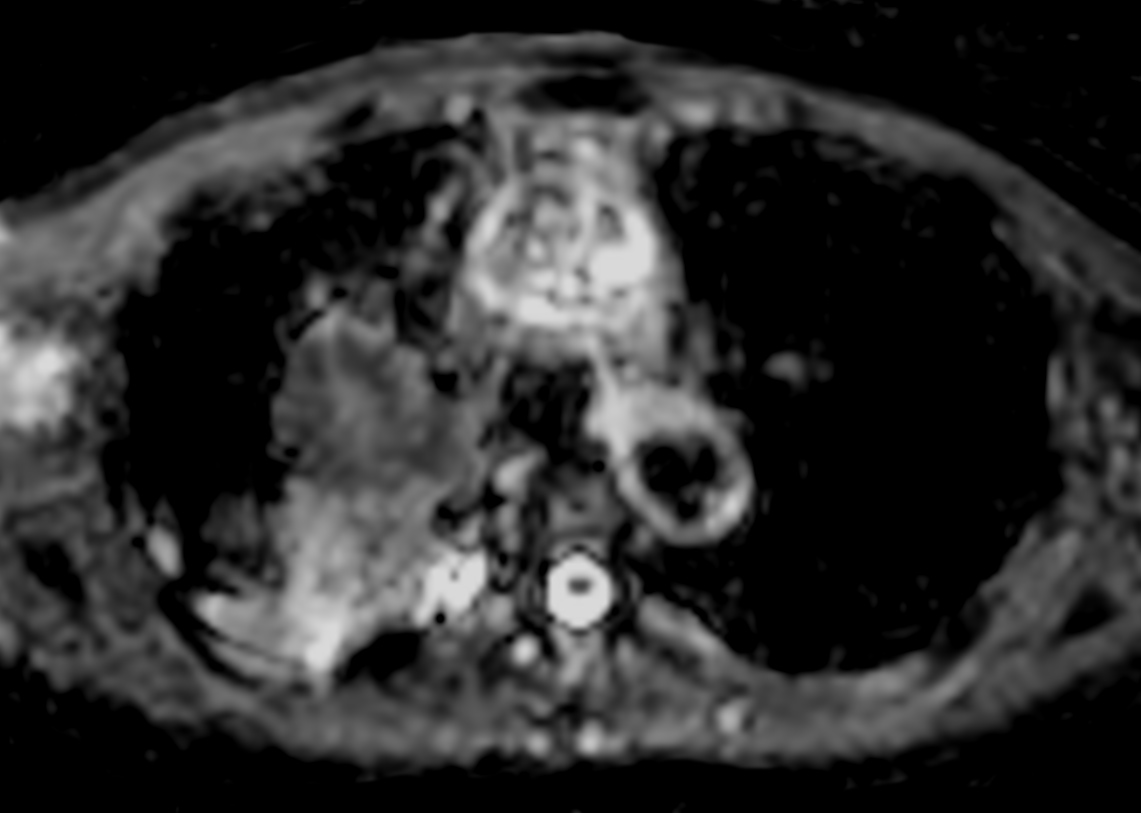

Patient with lung cancer. The ExamCard includes techniques for efficient fat-free imaging over large field-of-views (mDIXON XD), a diffusion procedure with less distortion (DWI TSE XD), a multi-phase contrast-enhanced sequence (4D FreeBreathing) to improve imaging confidence and Compressed SENSE to accelerate the entire exam.

DWI EPI b1000 (ADC)

DWI TSE XD b1000 (ADC) Compressed SENSE